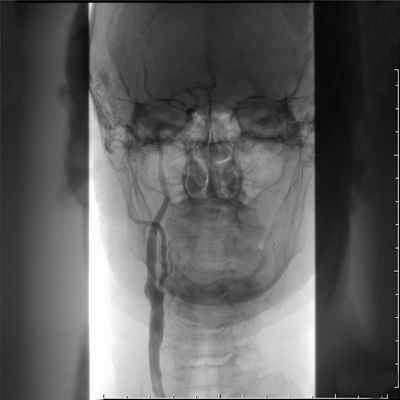

Указанных выше исследований достаточно для постановки диагноза. При решении вопроса об операции используют рентгеноконтрастное исследование. Показания к его проведению тождественны тем, которые используются при хирургическом лечении. Больным, которым не планируется оперативное вмешательство, ангиографическое исследование не проводят. Аортография выполняется по Сельдингеру (через непораженную бедренную или подмышечную артерию) или путем высокой транслюм-бальной пункции. Аортография позволяет оценить состояние дистально-го артериального и коллатериального русла, определить точную локализацию и протяженность окклюзирую-щего процесса. При выполнении аортографии брюшного отдела целесообразно делать снимки с захватом почечных артерий, поскольку почти у 1/3 пациентов с окклюзией терминального отдела аорты имеется артериальная гипертензия, которая может быть обусловлена стенозом почечных артерий. С этой же целью может использоваться МРА или электроннолучевая ангиография.

Большое значение имеет ангиографическое исследование с контрастированием сосудов. Обычно используют поясничную аортографию по методу Дос-Сантоса. Ее проводят следующим образом. Больного укладывают на живот на стол рентгеновского аппарата. Специальную иглу диаметром 1.8—2 мм под местной анестезией вкалывают на уровне I поясничного позвонка, на расстоянии 7—8 см от средней линии и проводят косо вверх. При медленном продвижении иглы удастся ощутить пульсацию аорты. О правильном попадании в просвет аорты свидетельствует появление из иглы пульсирующей струн крови. После этого в аорту вводят контрастное вещество и производят рентгеновские снимки. По аортограмме можно определить локализацию и протяженность окклюзии, составить представление о степени развития коллатерального кровообращения и судить о состоянии магистральных артерий нижних конечностей вплоть до голеней и стоп. В аорте наиболее часто поражается ее бифуркация. Реже верхняя граница закупорки достигает уровня отхождения нижней брыжеечной артерии.

Иногда окклюзнонный процесс распространяется даже до устьев почечных артерий. Это так называемые высокие, или инфраренальные, окклюзии брюшной аорты.